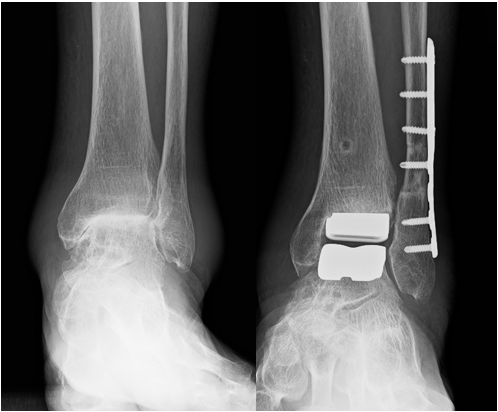

術前 術後

人工足関節置換術は、足関節を人工のインプラントに置換術手術法です。近年、本邦でも適応がひろがっています。

関節固定術に比較して足関節の動きを残せる利点があります。当院では、2018年から本邦で使用可能になった外側進入型人工足関節置換術を主に行っています。

腓骨骨切りを行い、外側からインプラントを挿入する方法で、骨を削る量を少なくすることが可能な手術法です。

通常は、手術後2週程度から短下肢硬性装具を使用して歩く訓練を開始し、1か月程度退院となります。当院ではご高齢の方を中心に積極的に取り組んでいます。